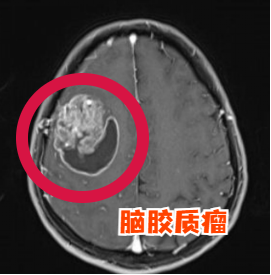

脑胶质瘤是指起源于脑神经胶质细胞的肿瘤,是最常见的原发性颅内肿瘤。

2021年版WHO中枢神经系统肿瘤分类将脑胶质瘤分为1~4级,1、2级为低级别脑胶质瘤,3、4级为高级别脑胶质瘤。

颅脑CT和核磁共振是最常用的两种无创检查方法,可以为医生提供患者脑部的图像。此外为进一步明确患者颅内肿瘤代谢以及与毗邻脑组织相应关系,可进一步完善磁共振功能成像、波普成像及血管成像。